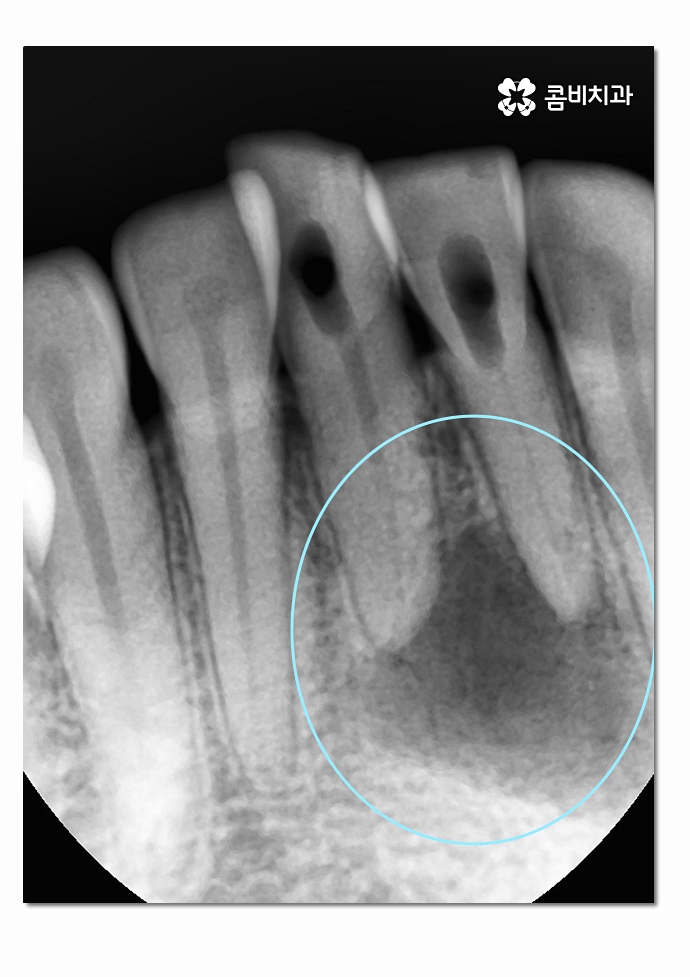

심한 경우에는 주변 치아에도 염증이 심해져서 여러 치아를

잃게 되는 사례도 종종 보는데 위 환자분의 경우에는

아랫니 2개까지만 멍울처럼 뿌리 끝에 염증이 심해진 상태를 볼 수 있어요.